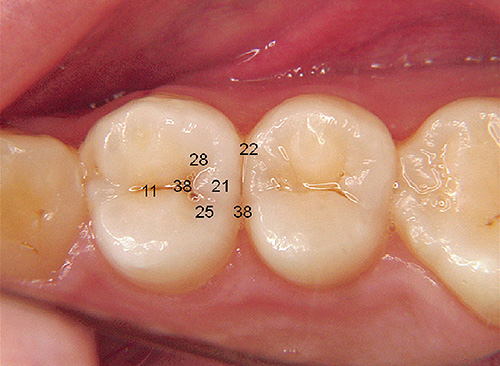

図1 患者の主訴は奥歯が変な感じがするということで、冷水、温水、打診痛もなかった。 -

図2 これを視診だけでどこがう蝕であるのかを判断することは難しい。小窩裂溝、舌側、隣接面の着色はう蝕と診断していいものか。Dental X‑rayを撮るにもどの歯に主軸を合わせるべきか考えてしまう。 -

図3 ダイアグノデント ペンを使用し咬合面の数値を計測すると、臼歯部は12~17で切削処置は必要なしと判断できた。 -